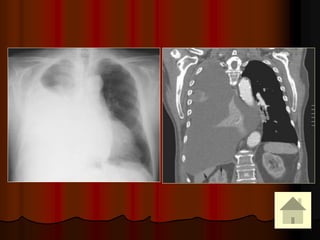

31-Oct-1435

A.J.Chandrasekhar,M.D.Chest X-ray Atlas.

HILUM OVERLAY SIGN: TERATOMA

Thymoma

Schwannoma